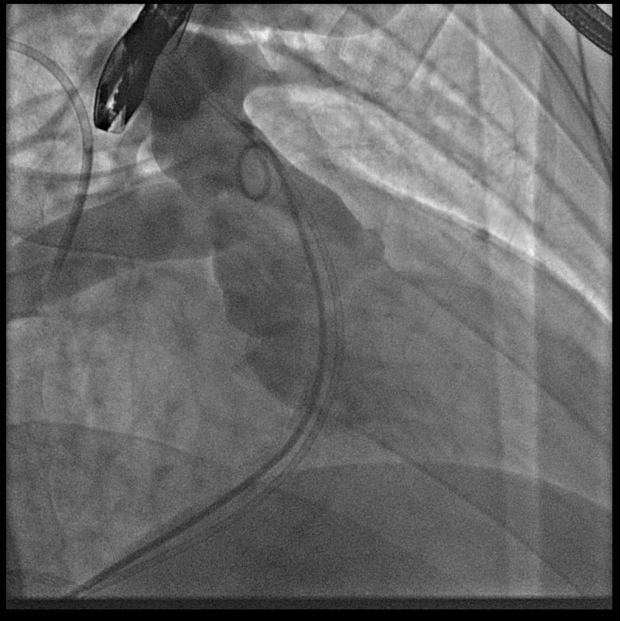

术中测量患者基础主动脉、肺动脉、右心室压力分别为111/58mmHg、31/4/13mmHg、34/1/6mmHg,通过肺动脉造影,术中测量球囊内径为32mm(见图二),选择36-25mm VENUS-P肺动脉瓣膜,在肺动脉造影指引下逐步打开瓣膜。考虑到患者肺动脉分叉较短,存在瓣膜释放后移位风险,故选择高位释放法(图三)。但释放瓣膜后造影提示右肺动脉开口局部被阻挡(图四),复测患者主肺动脉、左肺动脉、右肺动脉压力分别为57/13/25mmHg、55/12/24mmHg、27/7/14mmHg。

图二:术中扩张球囊刚好堵住右室流出道,测量球囊内经为32mm